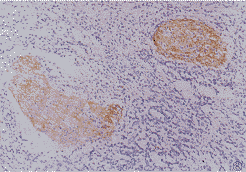

2.2 免疫组化法 bcl-2:仅有30%(6/20)的病例与正常皮肤交界处的瘤细胞为阳性染色(图6)。远离肿瘤的正常皮肤基底细胞胞浆呈黄色或棕黄色颗粒可作内对照。bax:全部病例呈阳性染色(图7)。染色强度频数分布见表1。

图6 与正常皮肤交界处的瘤细胞胞浆bcl-2呈现黄色或棕黄色颗粒.S-P×750

图7 bax 表达于胞浆、胞膜和核膜呈棕黄色。S-P×200

bcl-2是凋亡抑制原癌基因,其编码蛋白具有抑制细胞凋亡作用,但不影响细胞增殖。bax与bcl-2是同源基因,作用为促进细胞凋亡。野生型p53基因是一种抑癌基因,可诱导bax基因表达,抑制bcl-2基因表达〔6〕。细胞内bax和bcl-2基因产物共同构成了细胞内的微调变阻器(preset rheostat within cells)调节细胞凋亡。如一个细胞内bcl-2蛋白占优势,它结合掉所有的bax,余下的bcl-2相互接成bcl-2-bcl-2对,使细胞得以生存。反之,细胞则死亡〔7〕。本组病例中,bax占绝对优势,全部病例均为阳性表达,且以肿瘤中心最强,仅6例肿瘤边缘bcl-2呈阳性表达。与凋亡细胞分布吻合。相关性检验进一步表明瘤细胞凋亡与bax蛋白表达呈显著正相关,与bcl-2蛋白表达呈显著负相关。